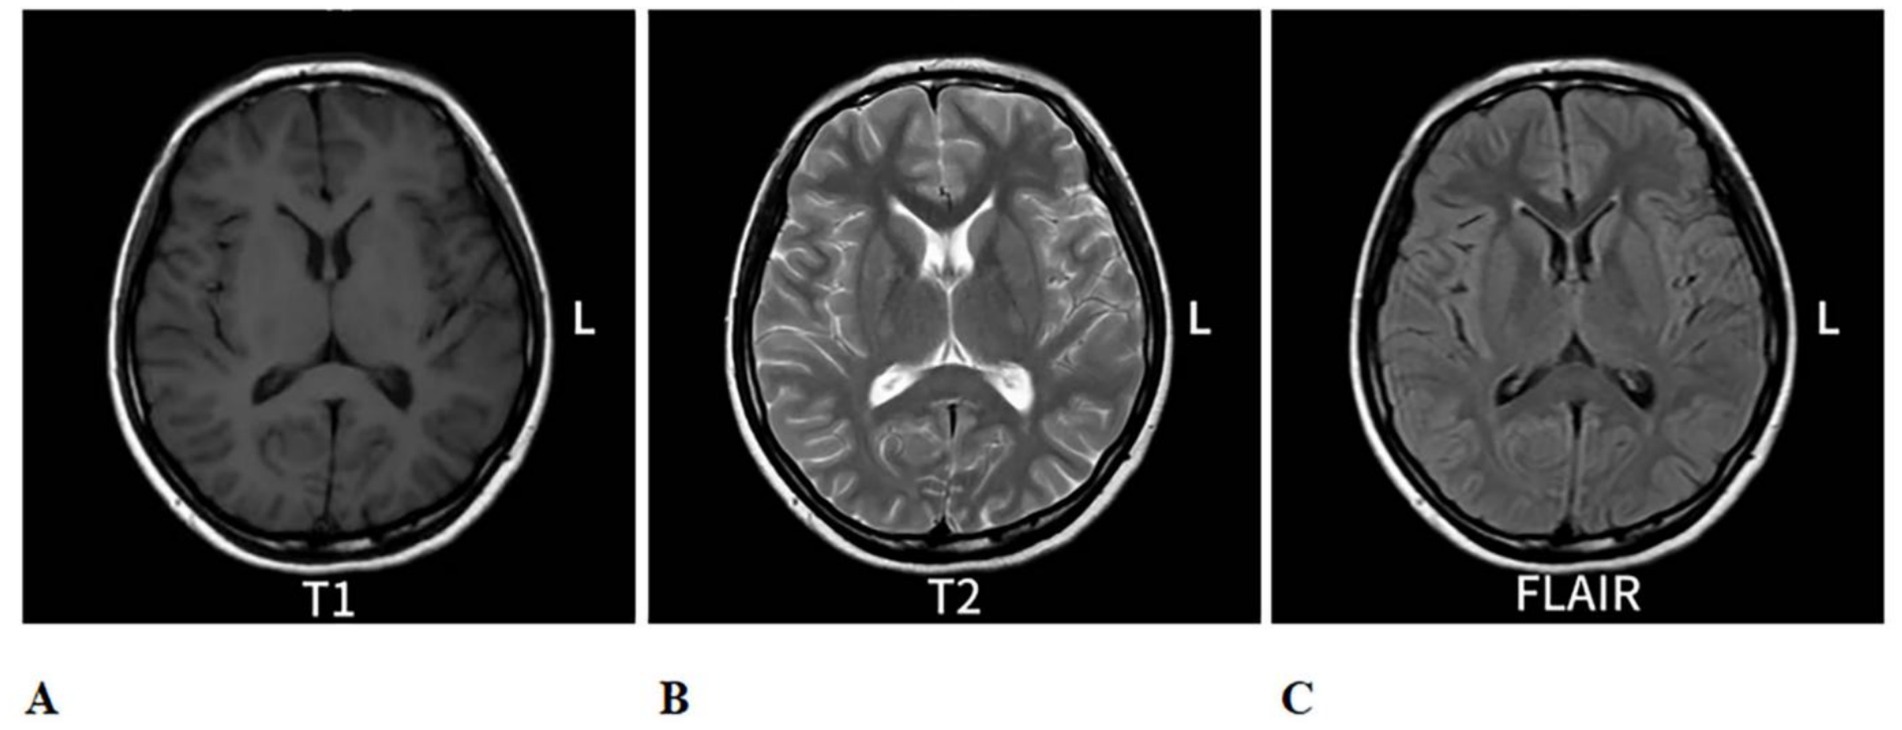

Figure 2

Re-evaluation of cranial MRI on 6 August 2024, compared to the MRI from 25 July 2024: The abnormal signal in the splenium of the corpus callosum. (A) is a T1-eighted image with low contrast. (B) is a T2-weighted image showing higher ontrast, highlighting fluid. (C) is a FLAIR image with intermediate contrast, uppressing fluid signals. Each scan shows axial brain views with symmetrical features.